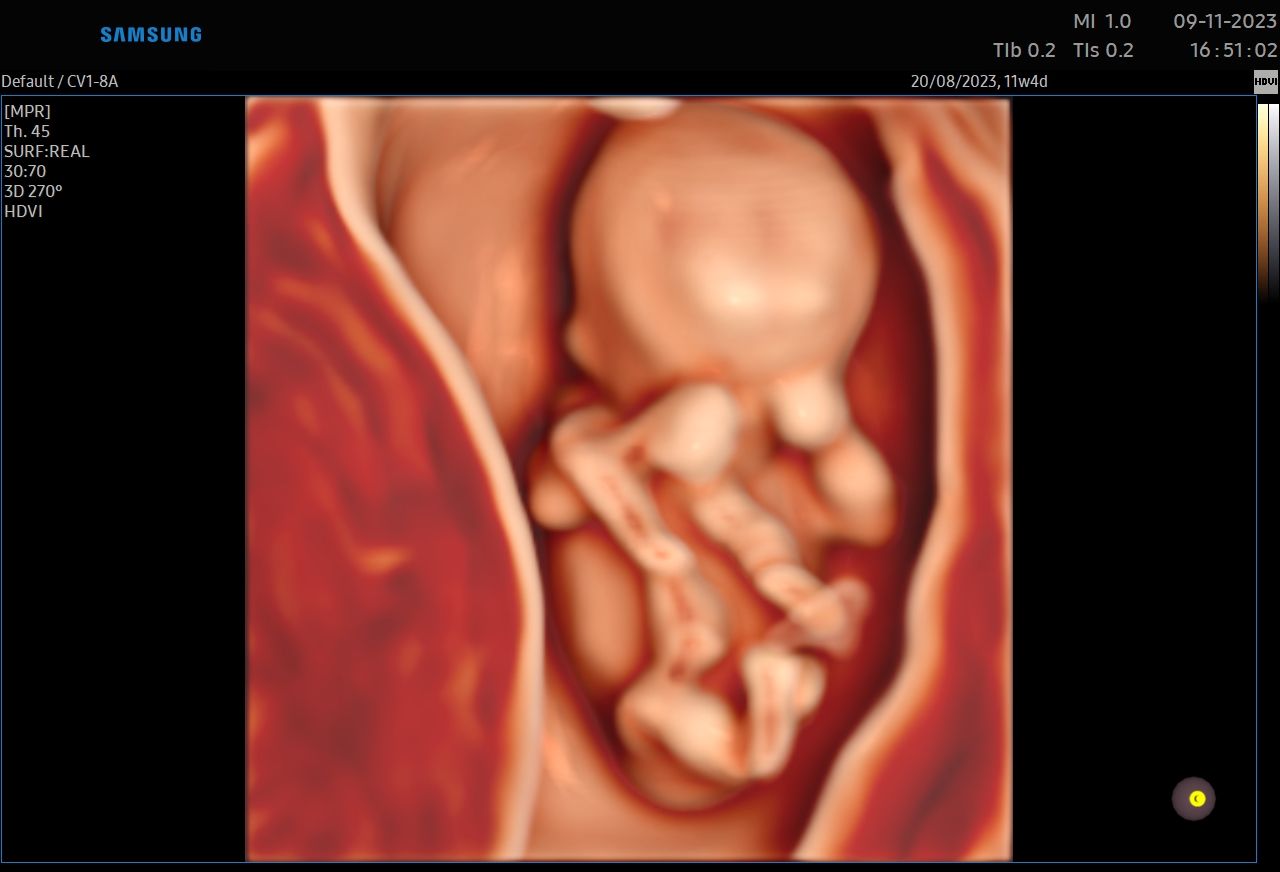

:-) Jestem lekarzem specjalistą w zakresie ginekologii i położnictwa , w ramach prowadzonej praktyki ginekologicznej staram się świadczyć kompleksowe porady lekarskie najwyższym poziomie ,w oparciu o najwyższe standardy jak i przy pomocy najnowszego sprzętu medycznego. W trakcie pracy zawodowej uzyskałem kolejno tytuły specjalisty I stopnia , a później specjalisty II stopnia , a także uzyskałem dodatkowe uprawnienia

CERTYFIKAT BADAŃ PRENATALNYCH POLSKIEGO TOWARZYSTWA GINEKOLOGÓW I POŁOŻNIKÓW

CERTYFIKAT BADAŃ PRENATALNYCH FMF ( FETAL MEDICINE FOUNDATION - LONDYN )

W ramach praktyki wykonuję pełen zakres badań ultrasonograficznych w zakresie ginekologii jak i położnictwa wraz z badaniami prenatalnymi , badaniami ultrasonograficznymi piersi .

Zdjęcia i filmy